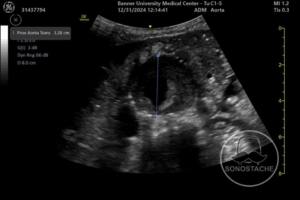

Case 3 – AAA